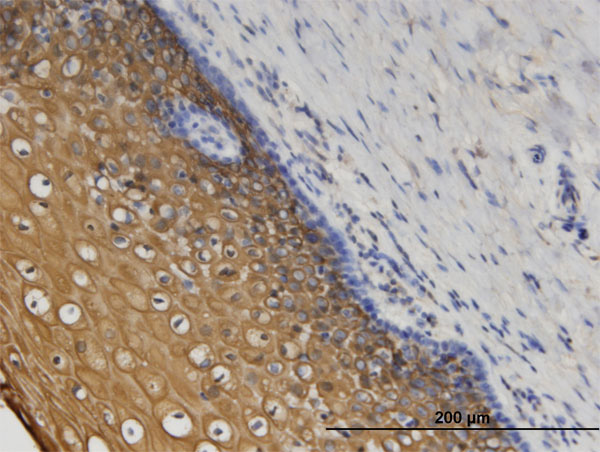

Immunoperoxidase of monoclonal antibody to CORO1C on formalin-fixed paraffin-embedded human uterine cervix. [antibody concentration 3 ug/ml] |